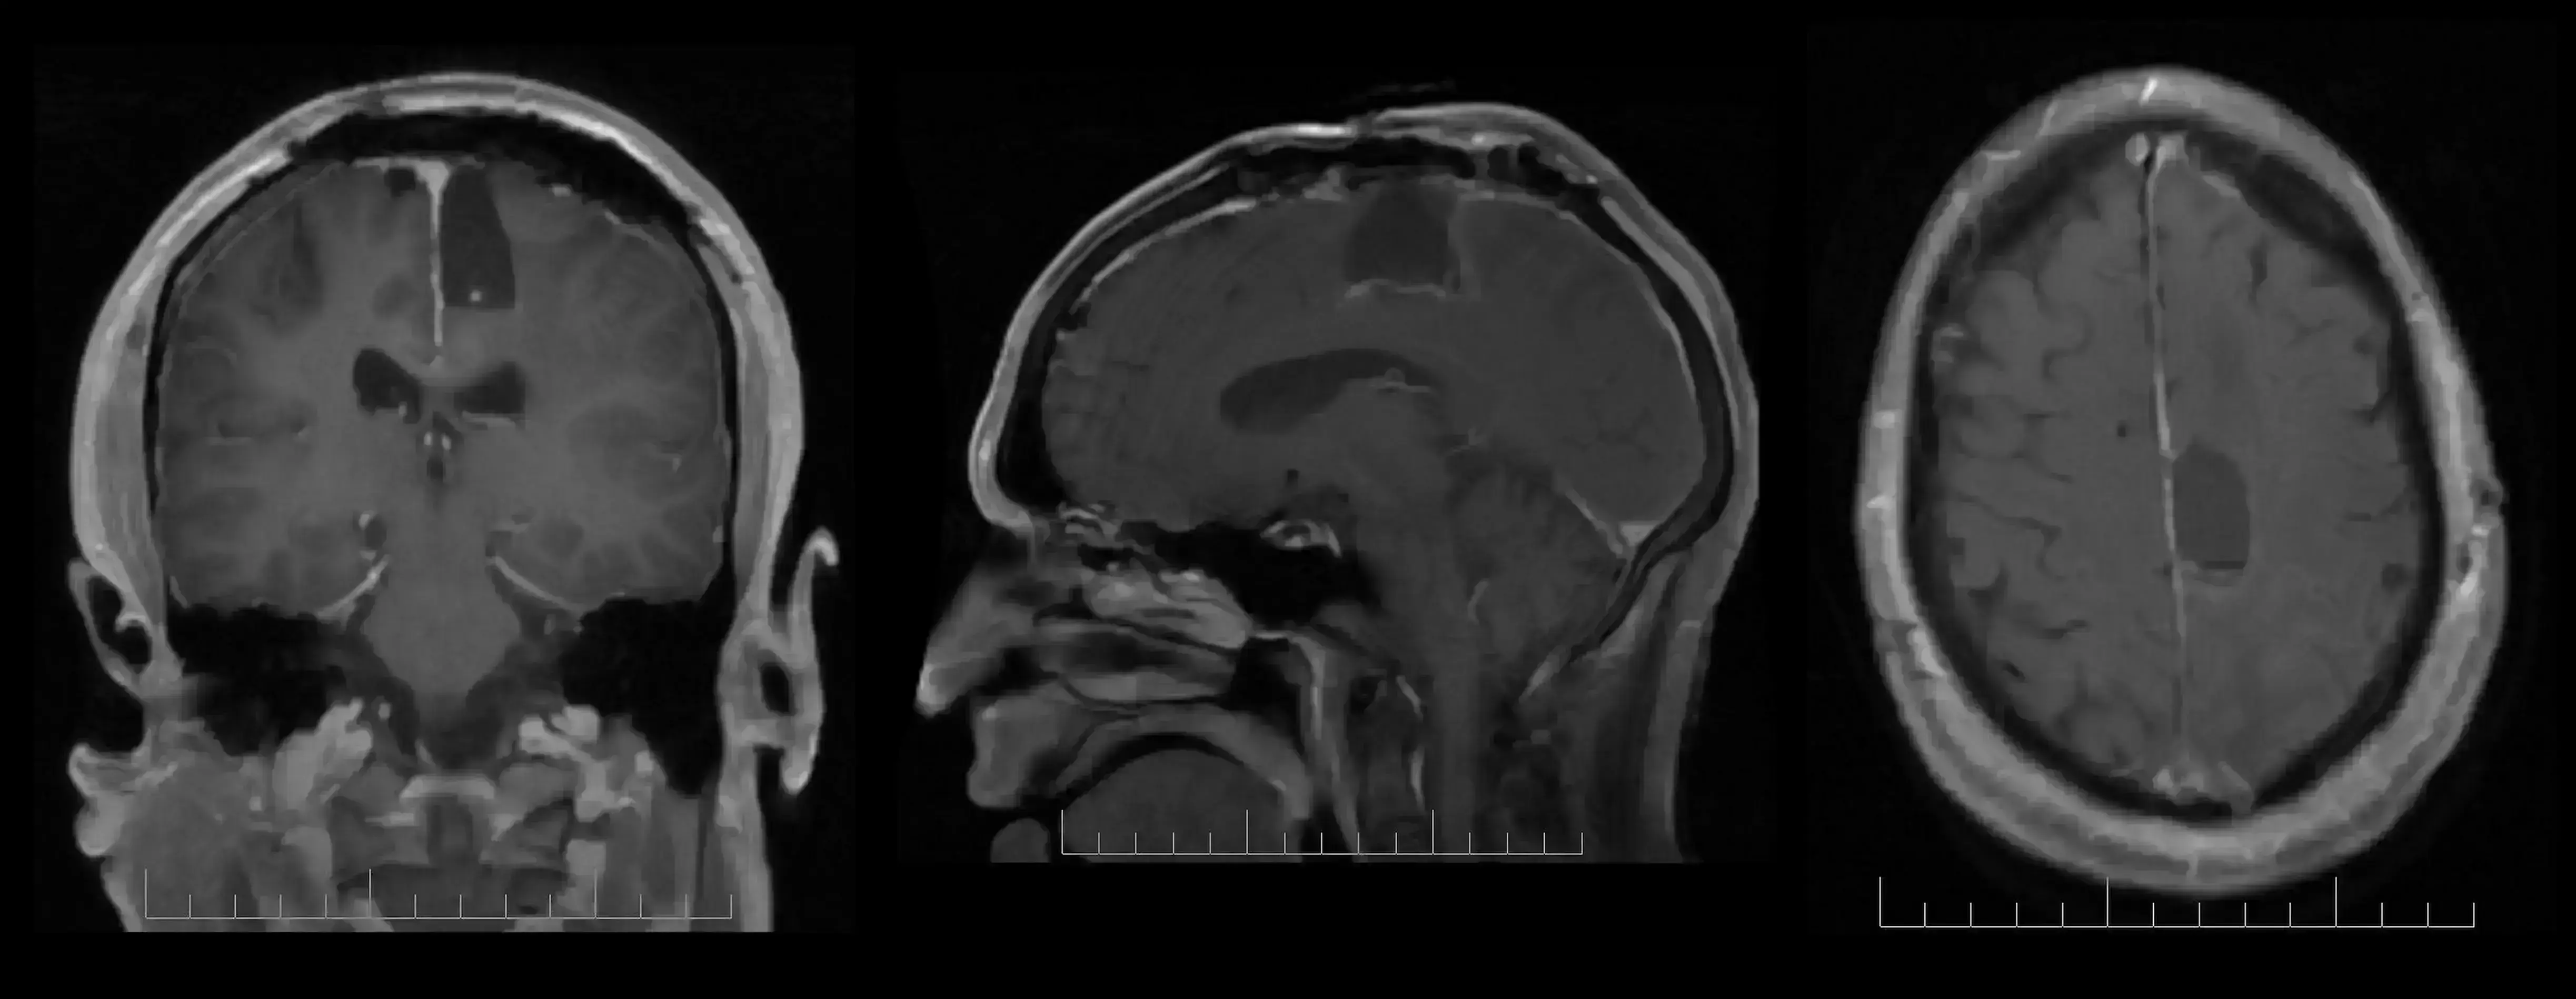

Embora consistentemente associados a alterações na massa cinzenta, nenhum dado prospectivo distinguiu os efeitos diferenciais dos medicamentos antipsicóticos, a partir da progressão da psicose no PEP. Sidhant Chopra, da Monash University, Austrália, apresentou os resultados de um estudo triplo-cego, controlado por placebo, prospectivo, que investiga as alterações na massa cinzenta em indivíduos medicados e não medicados acompanhando o PEP.

Os indivíduos selecionados com idade entre 15 e 24 anos receberam terapia psicossocial intensiva e foi dado um antipsicótico atípico ou placebo por 6 meses. Do total de 90 selecionados, 62 (32 com placebo; 30 com terapia ativa) foram submetidos à neuroimagem no início do estudo, aos 3 e aos 12 meses, assim como um grupo de 27 indivíduos saudáveis.

Ao longo de 12 meses, o medicamento antipsicótico atípica de baixa dose pareceu oferecer efeitos protetores sobre o declínio da massa cinzenta relacionado à doença visto no hipocampo e do giro supramarginal. As alterações volumétricas observadas no polo frontal, no córtex temporal medial, occipital, lateral e no cerebelo foram relacionadas à patologia da doença e não foram afetadas pelo medicamento em baixa dose. Um maior aumento volumétrico dentro do giro supramarginal foi associado a um melhor resultado sintomático, sugerindo um papel importante para esta região na mediação da recuperação específica de sintomas da psicose.